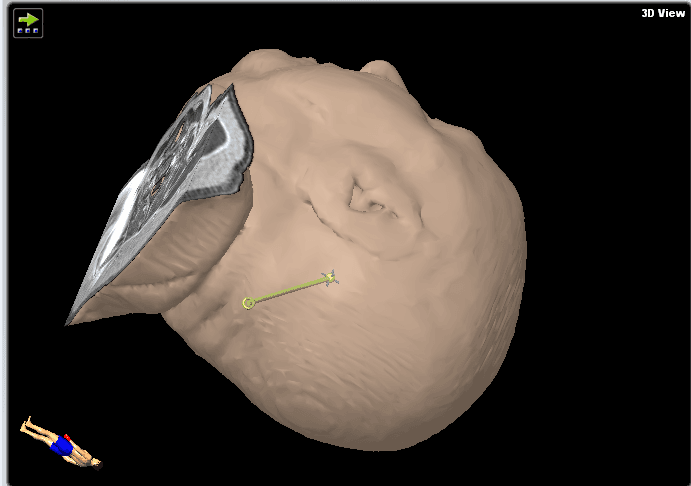

Abbiamo deciso di eseguire una biopsia cerebrale invece di un intervento chirurgico transcorticale aperto per testare la presenza di linfoma, per le ragioni esposte nella sezione sopra (Figura 3). La precisione del sistema di neuronavigazione è più precisa in posizione supina rispetto a quella prona grazie alla migliore visibilità del volto e della superficie convessità per la telecamera di navigazione. Abbiamo quindi optato per la posizione supina per consentire la massima precisione spaziale in questa procedura. La biopsia stereotattica sarebbe tecnicamente più difficile a causa della procedura basata sul telaio, che richiederebbe una posizione semi-seduta e un maggiore rischio di embolia atmosferica. Nelle lesioni puramente del tronco encefalico, la biopsia stereotattica basata su ronger sarebbe la tecnica più favorevole, causando meno traumi tissutali (ago biopsico più piccolo, ma anche minore volume di campioni). Il pavimento del quarto ventricolo deve essere evitato nelle procedure chirurgiche a causa del suo ruolo critico nella funzione del tronco encefalico.

Figura 3. Queste immagini mostrano il piano della traiettoria.